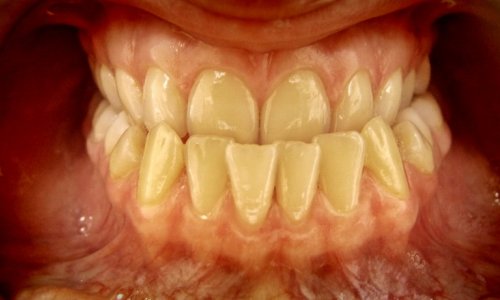

Zgryz Przed

Zgryz

Stan wyjściowy: Widoczna dysproporcja szczęk (progenia) wpływająca negatywnie na profil tkanek miękkich oraz funkcję żucia.